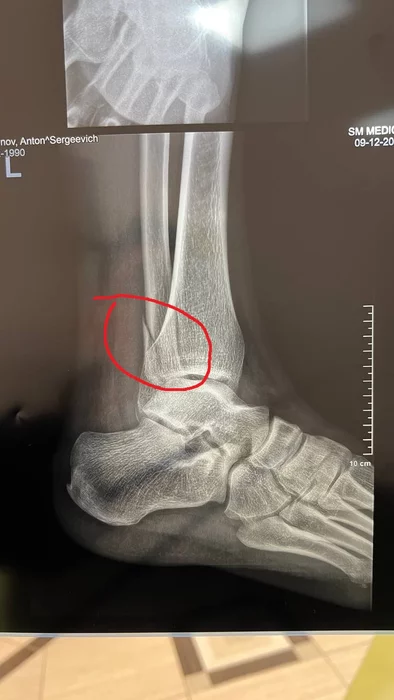

Впервые в жизни случился перелом. В 35 лет, пиздец, да? Я уж думал со мной такого не может произойти.

Упал со сцены, хорошо хоть не во время концерта) Надеюсь заживет само, а то чет уже на операцию намекают, за полтора месяца прогресс незначительный. Эх, вот бы выздоровление стало моим новогодним подарком в этом году)